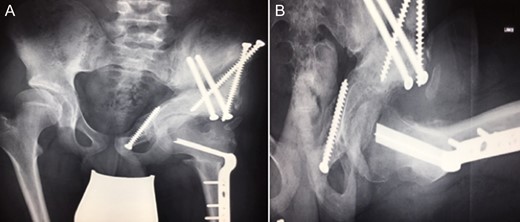

Ten years ago, a 12-year-old male presented to our clinic complaining about limping and massive swelling of the left hip. Figure 1 shows the initial X-ray and the 3D reconstruction of the left hip at first presentation when the femoral head, had already destroyed the lateral edge of the acetabulum like a mortar. Severe pain episodes have apparently not been noticed and a former hip dysplasia was not known. A brief clinical history revealed that the patient presented repeated episodes of finger biting and fevers from 2 to 8 years old. The intelligence level of the patient was at an average. The patient was admitted to a paediatric neurologist and a genetic test. A mutation of the NTRK1 gene was found and the diagnosis of CIPA was established. The right hip initially appeared to be normal and the patient was walking, therefore surgical reconstruction for the left hip was proposed due to massive swelling, inability of normal walking and significant limb length discrepancy. A Tönnis/Kalchschmidt triple pelvic osteotomy with open reduction and a shortening varus derotation osteotomy (VDRO) of the femur was performed (Fig. 2A–B). After 3 months the patient was walking again but another 3 months later the hip dislocated again without severe pain. Although the femoral head was already damaged the hip joint was reconstructed again by open reduction, capsular reconstruction with suture anchors and a trevira tube and a movable external fixator was used to temporary stabilize the joint (Fig. 3). The right hip at this time was still intact and was protected with a pneumatic orthotic device. A few months later in 2009, despite all surgeries, the left hip had entirely lost congruency and the right hip developed subluxation despite conservative treatment (Fig. 4). The patient was still walking so the decision to reconstruct the right hip with open reduction, capsular augmentation with a trevira tube, a triple pelvic osteotomy and VDRO was made (Fig. 5). Few months later this reconstruction failed as well and the hip dislocated without severe pain (Fig. 6).

(A + B): (2008) (A) Hip reconstruction with open reduction, Tönnis triple pelvic osteotomy and shortening rotational varus osteotomy of the left femur demonstrating correct deep reposition in ap view. (B) Lauenstein view shows that the acetabular congruency over the femoral head is restored.